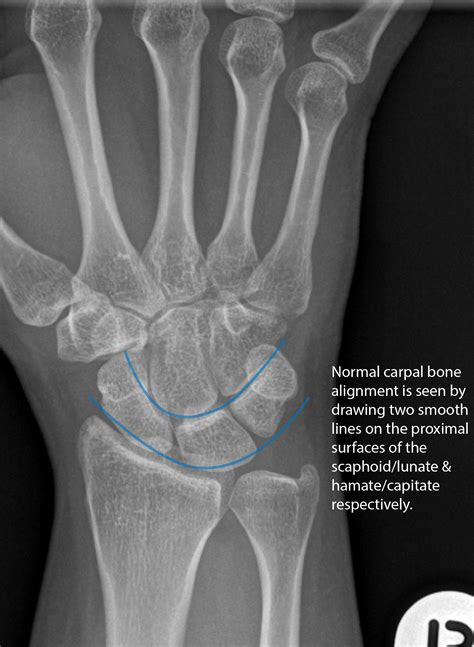

• Evaluating Joint Alignment: X-rays can help assess the alignment of the wrist joints, identifying dislocations or subluxations.

Interpreting the results of a Wrist Bones Xray requires the expertise of a radiologist or orthopedic specialist. The images will be reviewed to identify any abnormalities or injuries. Some common findings on a wrist X-ray include:

• Dislocations: Misalignment of the bones in the wrist joint.